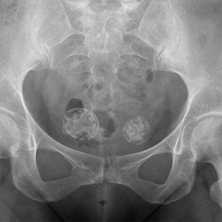

МРТ костей таза что показывает

Таз - часть скелета человека, обеспечивает прикрепление к туловищу нижних конечностей, является опорой и вместилищем для органов. Симптомы патологических процессов в указанной зоне, вне зависимости от природы, схожи. МРТ костей таза - ведущее исследование для выявления причины заболеваний костно-мышечной системы.

Магнитно-резонансная томография демонстрирует подвздошную, лобковую, седалищную кости, симфиз (спереди) и копчик (сзади), тазобедренные суставы, внутренние органы (мочевой пузырь, простату, матку, часть кишечника и пр.)

Сначала чаще используют компьютерную томографию. При сохранении необъяснимой боли в течение недели без видимых рентгенологических признаков показано выполнение магнитно-резонансного сканирования. Процедура важна для диагностики угрожающих состояний: аваскулярного некроза, злокачественного опухолевого процесса и пр. МР-томография демонстрирует максимально подробные изображения мягкотканных структур: мышц, связок, сухожилий, нервно-сосудистых пучков, что необходимо для определения правильного диагноза и дифференциации ряда суставных синдромов.

МРТ: симфизит, стрелка указывает на утолщение капсулы, неровность контуров

МРТ костей таза показывает множественные очаги, что говорит о метастатическом поражении